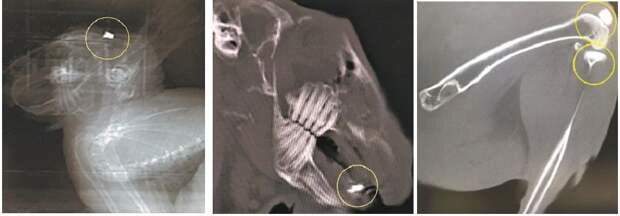

Он также может стать основой для современных костных имплантатов.Обычно для имплантирования костных тканей используют титан, так как он устойчив к воздействию химической или биологической среды живого организма. Однако использование титана делает более хрупкими близлежащие кости. Созданный российскими учеными сплав решает эту проблему, так как воспроизводит поведение заменяемой кости под нагрузкой.